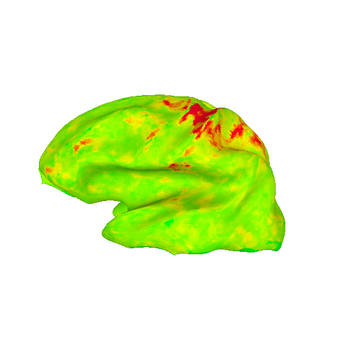

These images show lateral views of surface models. The colors represent the F-statistic at each surface node for each of the motion and distortion correction methods. While there are differences between the images, they are subtle.